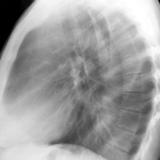

RLL Collapse  1 Lateral